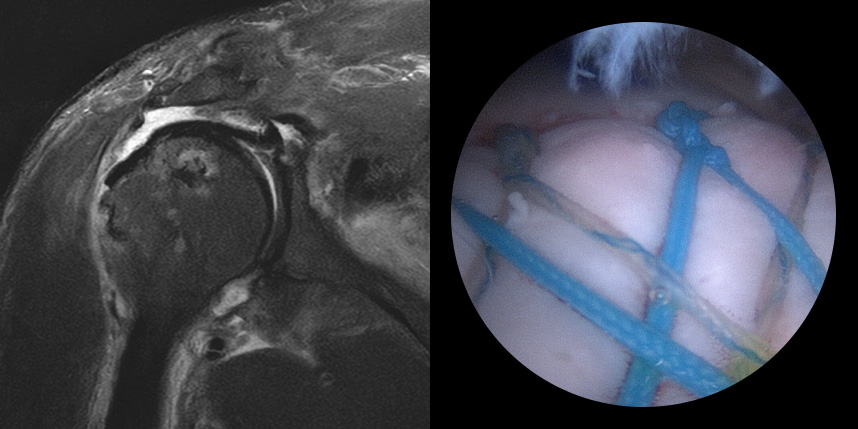

브릿지 봉합술

접촉면접과 힘줄

부착 압력이 높습니다.

초기,중기,말기 파열에

주로 사용됩니다.

상대적으로

재파열율이 낮습니다.